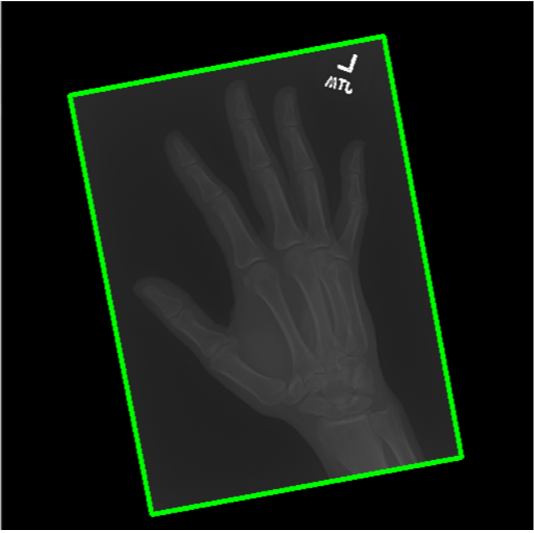

The first step in our pipeline is to detect the X-ray image carrier in the image. To this end, we apply OpenCV’s contour detection using Otsu binarization [14], and retrieve the minimum size bounding box, which does not need to be axis-aligned. This works sufficiently well as long as the majority of the image carrier is within the image (cf. Figure 3). However, the approach might fail for heavily tilted images or those where larger parts of the image carrier reach beyond the image border.

To further improve the detection of hands, and in particular split the images where two hands are depicted on one image, we manually labeled approximately 150 bounding boxes in the images. Using this small dataset, we fine-tune a pre-trained single shot multibox detector (SSD) [12] with MobileNet as taken from TensorFlow. An exemplary results can be seen in Figure 3.